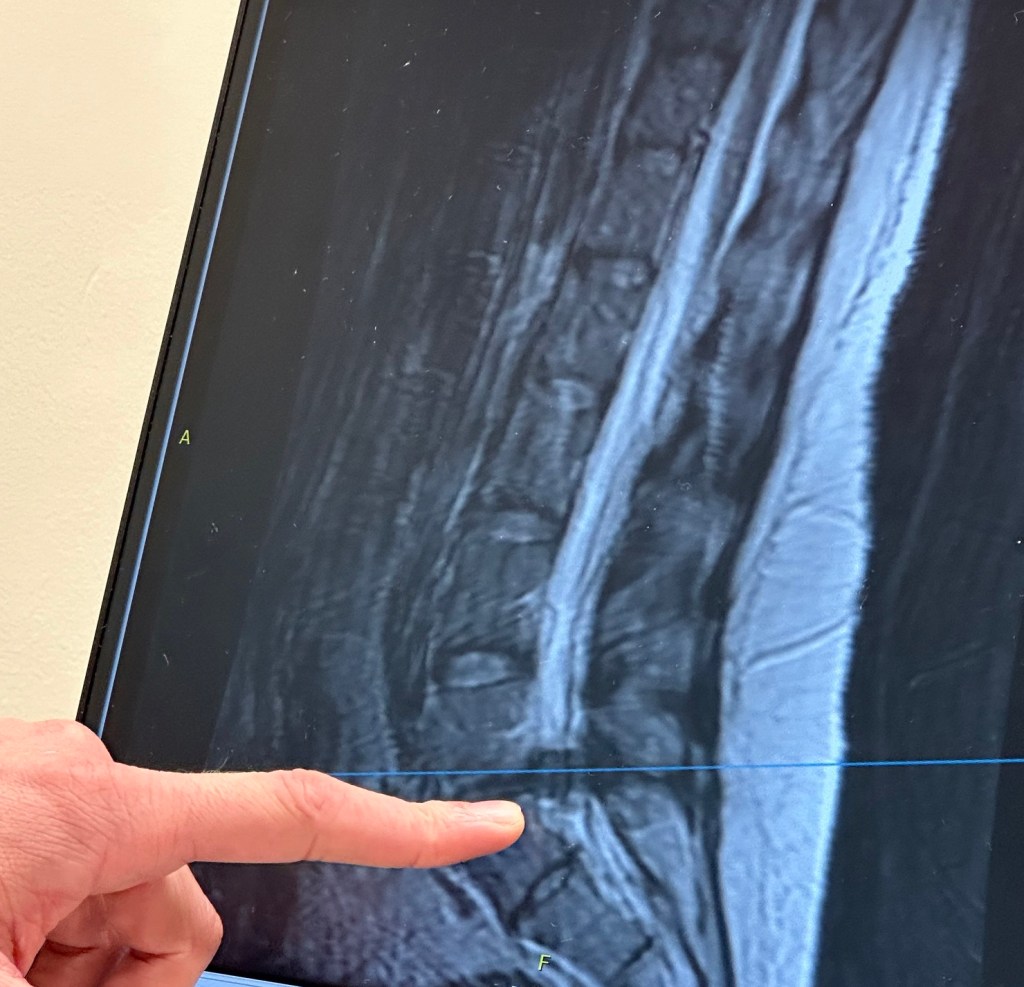

Hi, I’m Stephanie, a mom of two, passionate about teaching, photography, and travel. This is my blog documenting my battle with Cauda Equina Syndrome.

Hi, I’m Stephanie. I am a reading specialist, dyslexia practitioner, and a mom of 2. I am passionate about education, travel, and photography. This site documents my current battle with Cauda Equina Syndrome.